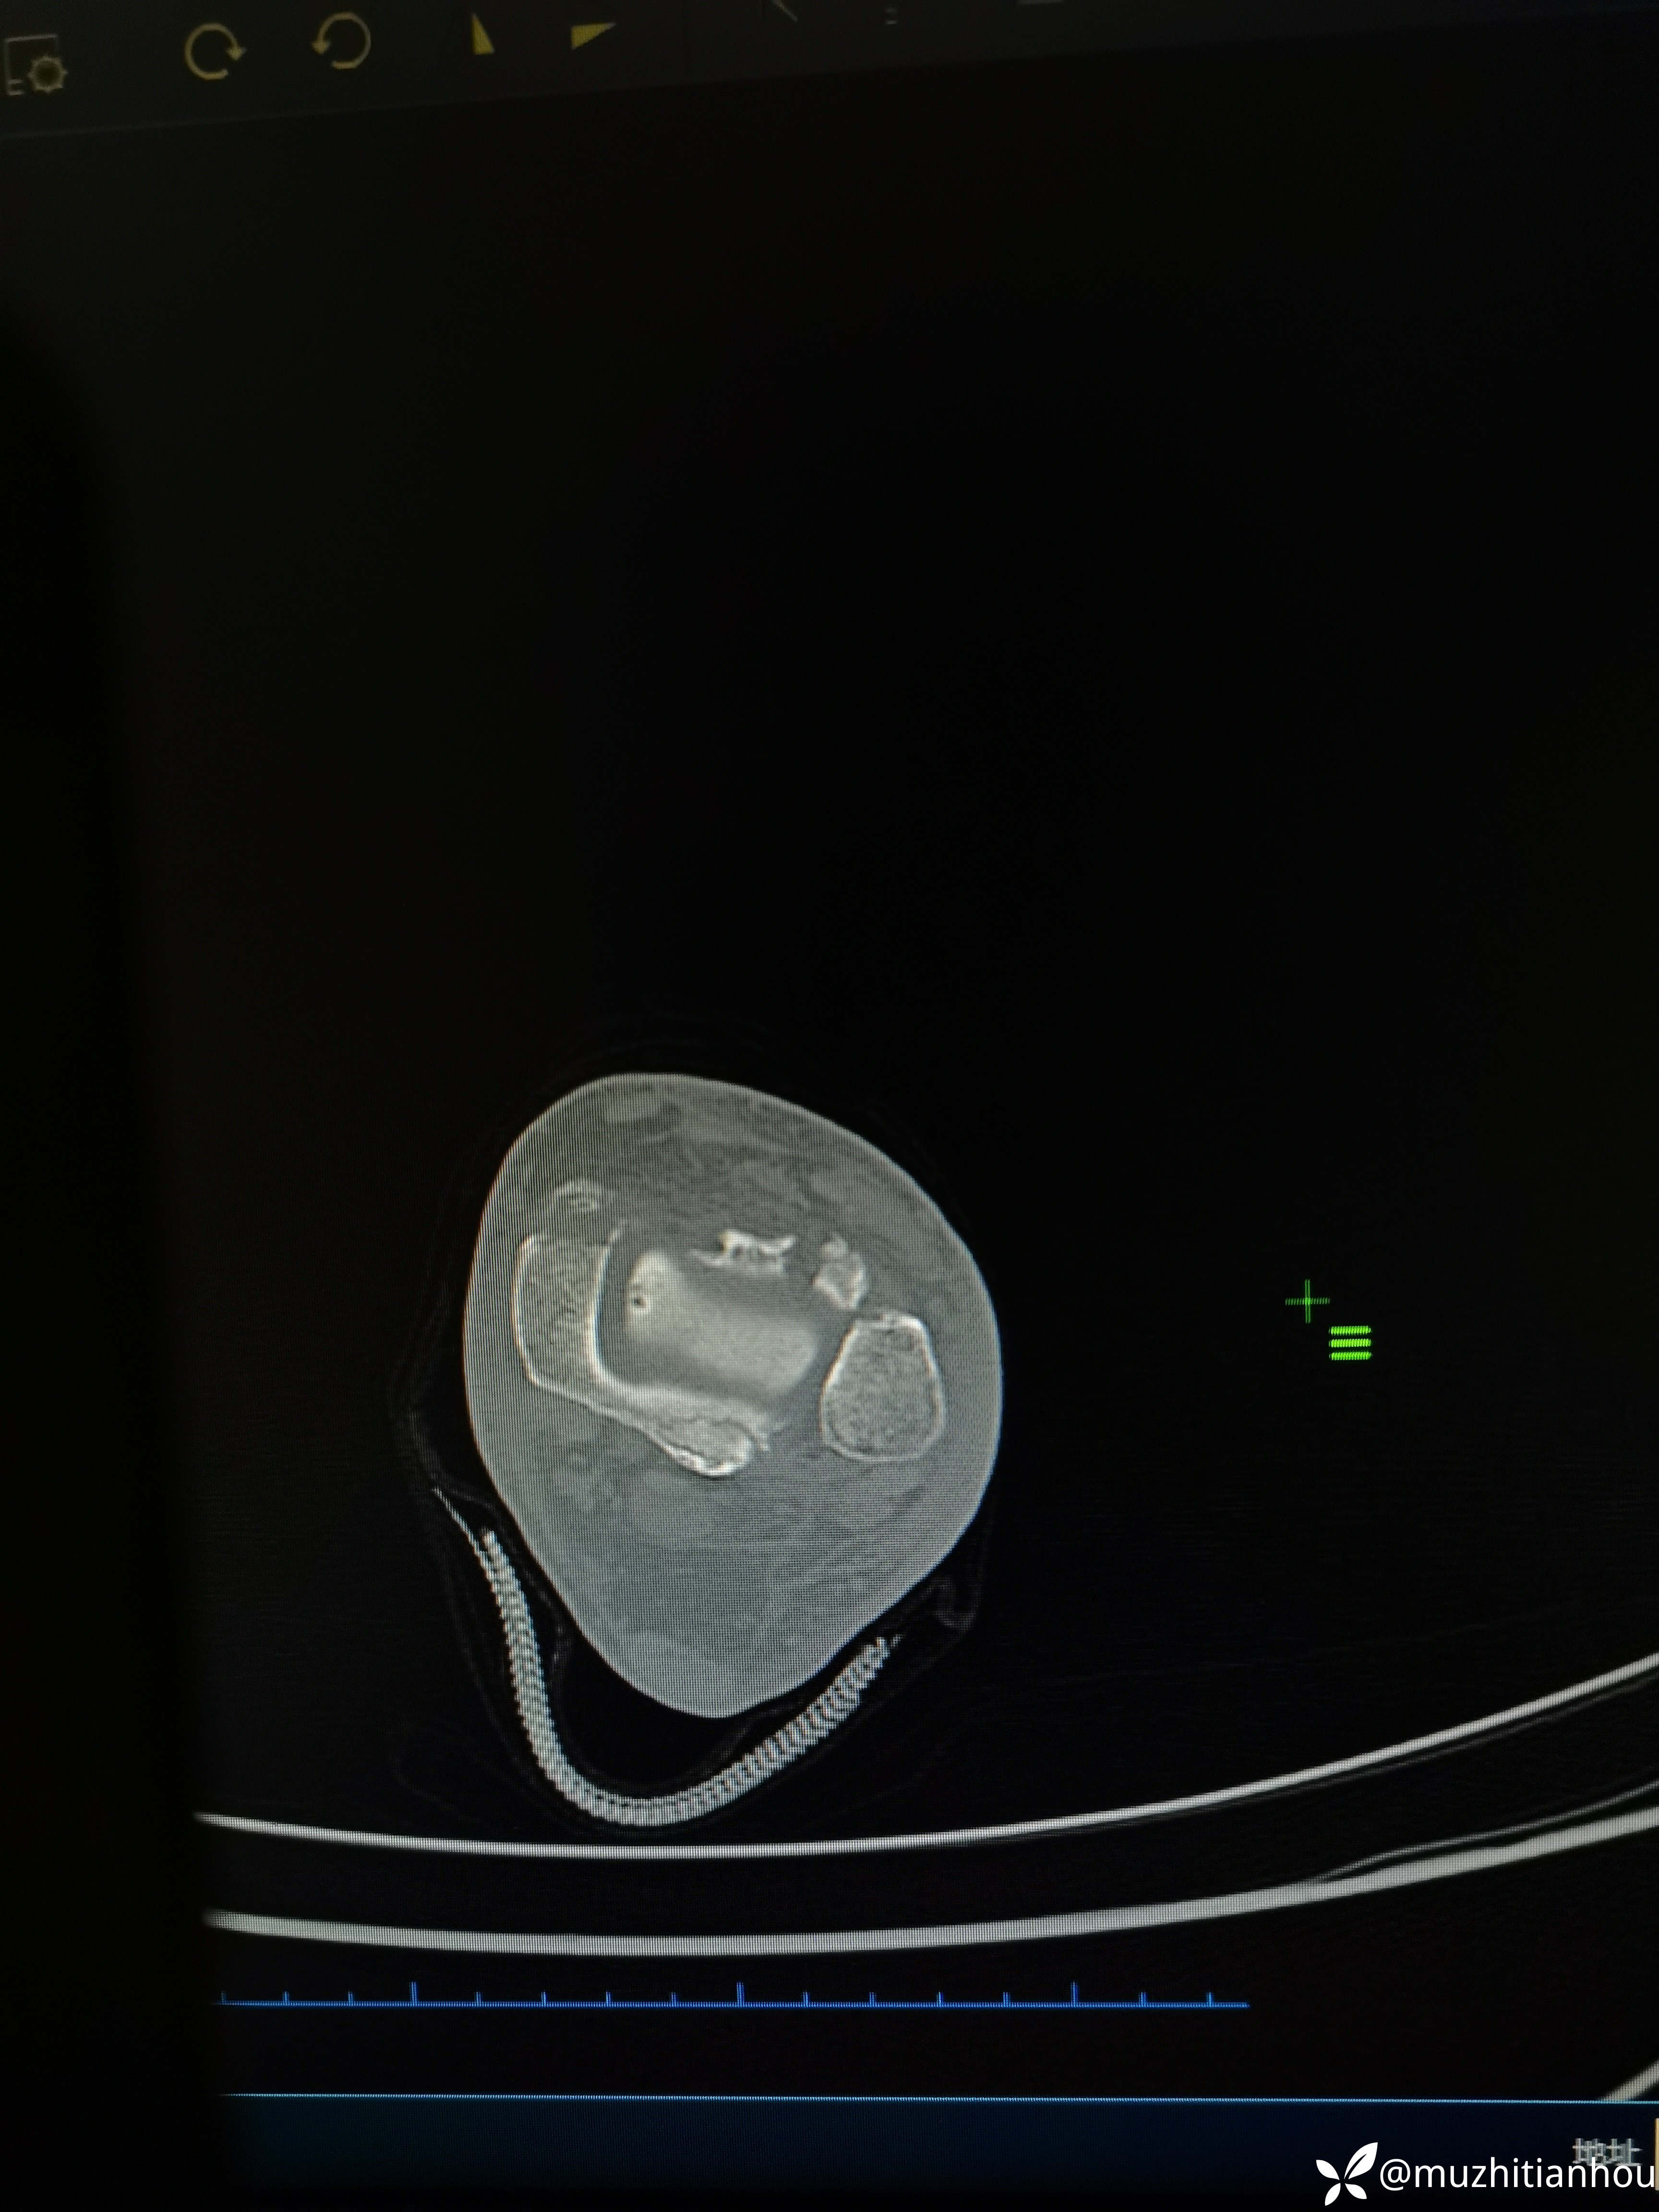

讲明白道理后取得患者信任,入院做了三维CT真像慢慢浮出水面,看到这个您是不是觉得收获很大

三维重建来的更直观,Tillaux骨块的分型和处理选择大家是否铭记在心呢?我想大多数人跟我差不多,回头去复习下吧。收获会很大

沈通氏线中段,tillaux骨块累及到下胫腓

最后诊断清楚了,手术方案如何定呢?外踝后外侧大弧形切口钢板固定外踝后往前方剥离显露Tilaux骨块然后固定?还是前外侧切口处理?还是外踝微创插板固定,Tillaux骨块正前方单独切口固定?选择什么固定?4.5空心钉?3.0哈勃特钉?还是?内踝就不说了常规空心钉固定吧。下胫腓需要固定吗?欢迎各位老师指教。